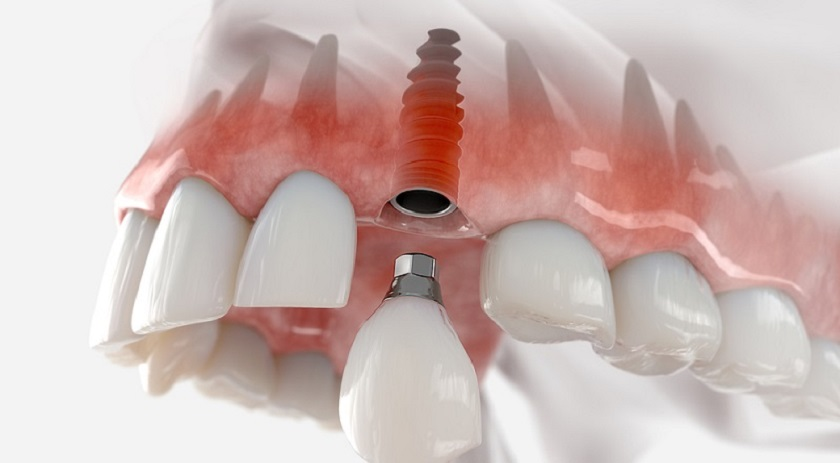

Cấy ghép Implant là phương pháp hiện đại giúp khôi phục răng đã mất với độ bền cao, thẩm mỹ tự nhiên và chức năng ăn nhai tối ưu.

Khôi phục cấu trúc răng toàn diện

Trụ Implant thay thế chân răng mất, tái tạo đầy đủ cấu trúc răng – nướu – xương, đảm bảo ăn nhai và phát âm tự nhiên.

Cấy trụ Implant vào xương hàm

Thực hiện phẫu thuật trong môi trường vô khuẩn tuyệt đối; bác sĩ đặt trụ Implant titanium vào vị trí đã xác định với kỹ thuật ít xâm lấn – không đau – an toàn tối đa.

Lắp răng sứ và kiểm tra khớp cắn

Phục hình răng sứ trên Implant, điều chỉnh khớp cắn chuẩn xác, đảm bảo thẩm mỹ, chức năng ăn nhai và độ bền lâu dài.